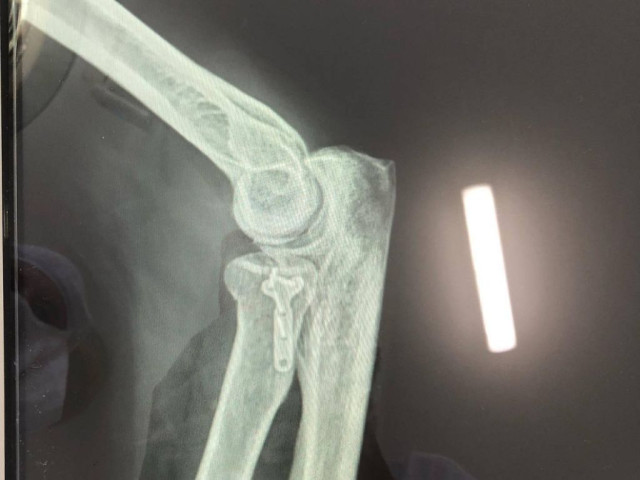

Після проведеного обстеження пацієнту було встановлено діагноз: перелом голівки променевої кістки, про це пишуть на фейсбук-сторінці медзакладу.

Хворому відновили конгруентність суглобових поверхонь та остеосинтез голівки променевої кістки. Операція пройшла успішно.